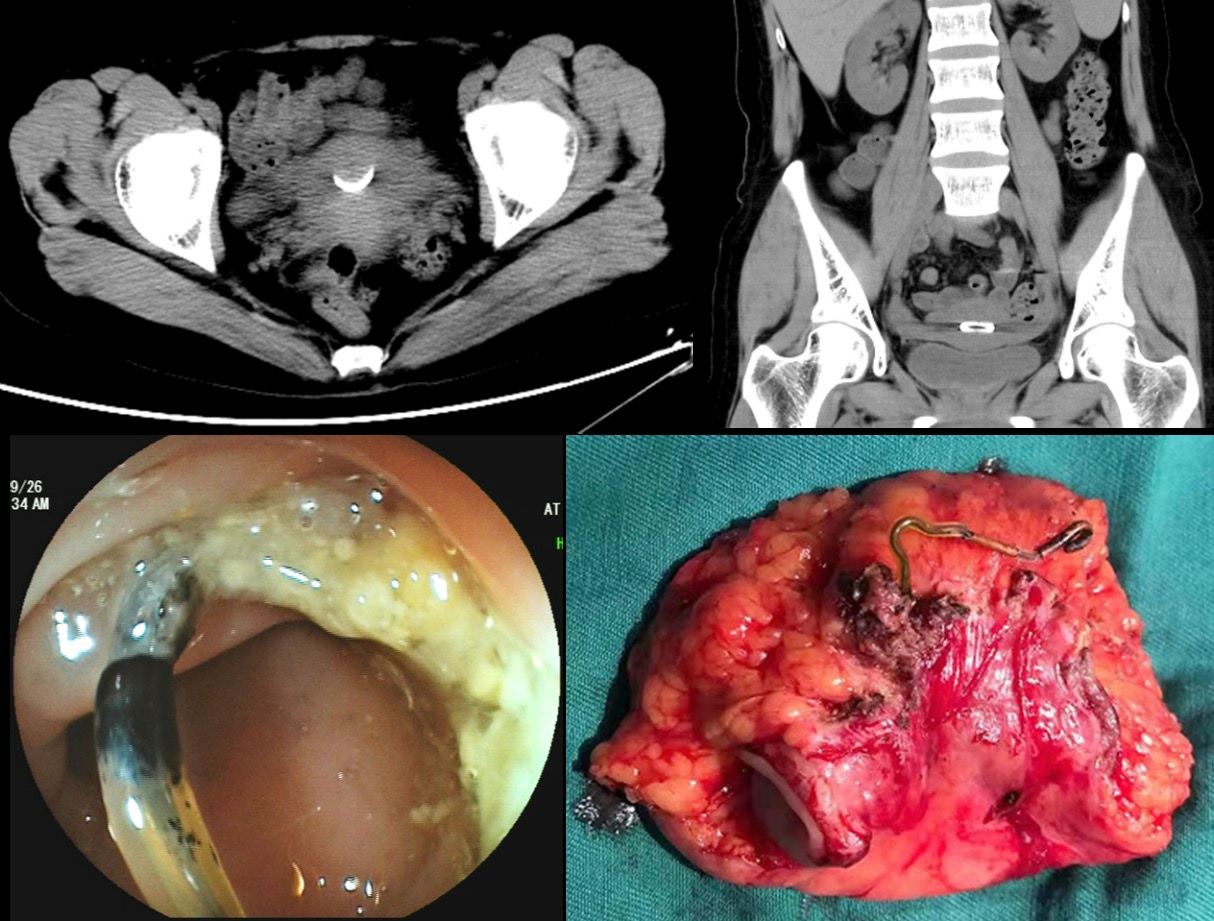

A 38-year-old woman was transferred to our hospital with a 10-day history of lower abdominal pain and vomiting. She had no significant surgical and medical history. Physical examination showed no specific abnormality. Computed tomography of the abdomen and pelvic cavity incidentally showed a thin, irregular foreign object embedded in the right lateral wall of the rectum (Figure 1A and 1B). Colonoscopy confirmed perforation of the rectum by a thin metallic object (Figure 1C). On detailed questioning, she recalled having an intrauterine device inserted 9 years ago. The patient received the diagnosis of rectal perforation by an intrauterine device. The device was successfully removed laparoscopically by performing a partial rectectomy (Figure 1D). The postsurgical course was uneventful and she became asymptomatic after the procedure. As a safe and effective birth control method, insertion of intrauterine contraceptive device is very popular in China. However, the migrated device may present as bleeding, abdominal pain, and even colonic perforation although most of the perforations are asymptomatic [1]. Migrating intrauterine contraceptive devices are usually involved in the sigmoid colon, which is the most commonly penetrated part of the colorectum [2]. As a rare complication of intrauterine device insertions, Uterine perforation may subsequently result in rectal perforation in our case. Minimally invasive techniques such as colonoscopy and laparoscopy are usually performed to remove the device eroding the colon wall [3].